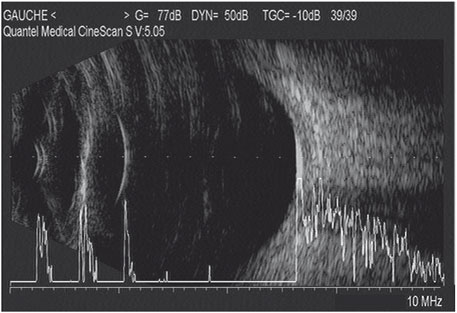

Pendant de nombreuses années, les biomètres les plus utilisés ont été les appareils d’échographie en mode A qui traduisent en pics de différentes hauteurs les structures plus ou moins échogènes traversées par le faisceau ultrasonore (fig. 14-2).

Fig. 14-2 Échographie mode A.

Exemple de biométrie en mode A qui identifie les pics des différentes interfaces avec des montées très abruptes témoignant d’une bonne perpendicularité du faisceau ultrasonore par rapport aux interfaces du cristallin et de la rétine. Cet élément est un gage de fiabilité de mesure.

Classiquement, un échogramme de biométrie le plus fiable possible doit montrer des pics principaux, cristalliniens et rétiniens, les plus hauts possibles. La conversion de l’échogramme A en mesures de distance se fait par positionnement de repères qui identifient différents secteurs intraoculaires dans lesquels les ultrasons se propagent à une vitesse connue. Les appareils les plus utilisés ont quatre repères pour identifier trois segments intraoculaires (tableau 14-I) :

– le segment compris entre la face antérieure de la cornée et la face antérieure du cristallin est converti en distance selon une vitesse de conduction des ultrasons de 1 532 m · s–1 ;

– le segment cristallinien est converti selon une vitesse de conduction de 1 641 m · s–1 ;

– le segment vitréen est converti selon une vitesse de 1 532 m · s–1.